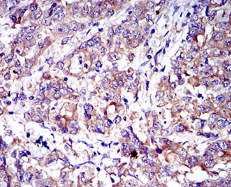

CD6 Mouse Monoclonal antibody[6B9E6]

IHC    1/200 - 1/1000